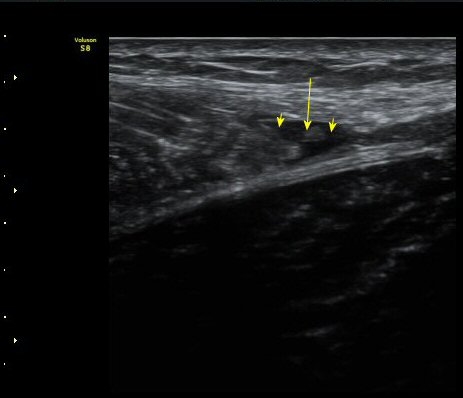

¼ö»ó ÈÄ 3ÁÖ Â°

1ÁÖ Àüº¸´Ù´Â ÀûÁö¸¸ ºñº¹±Ù°ú °¡Àڹ̱٠»çÀÌ¿¡ Ç÷¾×ÀÌ °í¿© ÀÖÀ½(±×¸² 8. 9)

ÃÊÀ½ÆÄ À¯µµÇÏ¿¡ Ç÷¾× ÈíÀÎ ÈÄ(µ¿¿µ»ó) Ç÷¾×ÀÌ ¸ðµÎ Á¦°Å µÈ(±×¸² 10) ÈÄ Åº·ÂºØ´ë·Î

¾Ð¹ÚÇÏ¿© µÎ ±ÙÀ°ÀÇ ¾ÐÂøÀ» À¯µµÇÔ.